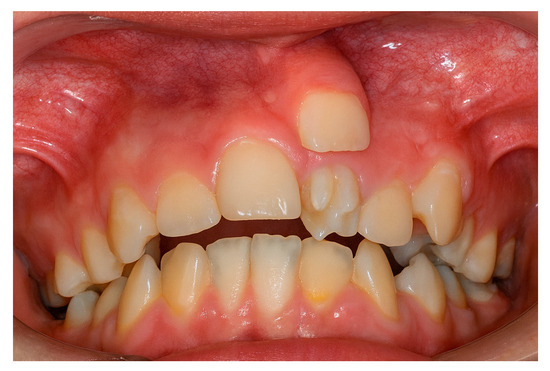

Background: Supernumerary teeth (ST) are developmental anomalies that may interfere with eruption, alignment, and occlusal balance. Their etiopathogenesis and management remain controversial. This multicentric study aimed to evaluate the epidemiological, morphological, and radiographic features of ST in a Romanian population and identify impact predictors. Methods: Between January 2020 and March 2025, 153 consecutive patients (91 males, 62 females; mean age 14.8 ± 6.2 years) with clinically and radiographically confirmed supernumerary teeth were evaluated across three Romanian academic centers: the University Dental Clinic, George Emil Palade University of Medicine, Târgu Mureș (n = 78 patients); the Department of Periodontology, Lucian Blaga University of Sibiu (n = 45 patients); and the Department of Dentistry, Dimitrie Cantemir University of Târgu Mureș (n = 30 patients). Results: A total of 185 ST were recorded, most frequently conical (48.6%) and mesiodens (56.2%). Complications were observed in 40.5% of patients. Multivariable analysis identified Angle Class III malocclusion (OR = 1.89; p = 0.039) and tuberculate morphology (OR = 2.93; p = 0.021) as the strongest independent predictors of impaction, alongside associations with younger age (<13 years) (OR = 3.12; p = 0.003) and male gender (OR = 1.78; p = 0.046). CBCT demonstrated high diagnostic concordance with OPG (κ = 0.89), but showed superior performance for complex cases, identifying 11 root resorptions and 9 vestibulo-palatal displacements that OPG missed. Multivariable analysis identified Angle Class III malocclusion (OR = 1.89; p = 0.039) and tuberculate morphology (OR = 2.93; p = 0.021) as the strongest independent predictors of impaction, alongside associations with younger age (<13 years) (OR = 3.12; p = 0.003) and male gender (OR = 1.78; p = 0.046). Conclusions: This multicentric study provides updated Romanian data and highlights novel risk factors and diagnostic selection guidelines that may support individualized treatment planning. Angle Class III malocclusion is a novel and critical independent predictor of supernumerary tooth impaction, alongside tuberculate morphology. This finding strengthens the rationale for utilizing CBCT specifically in Class III patients with ST to pre-emptively manage complex impactions and associated pathology. Full article

Figure 1